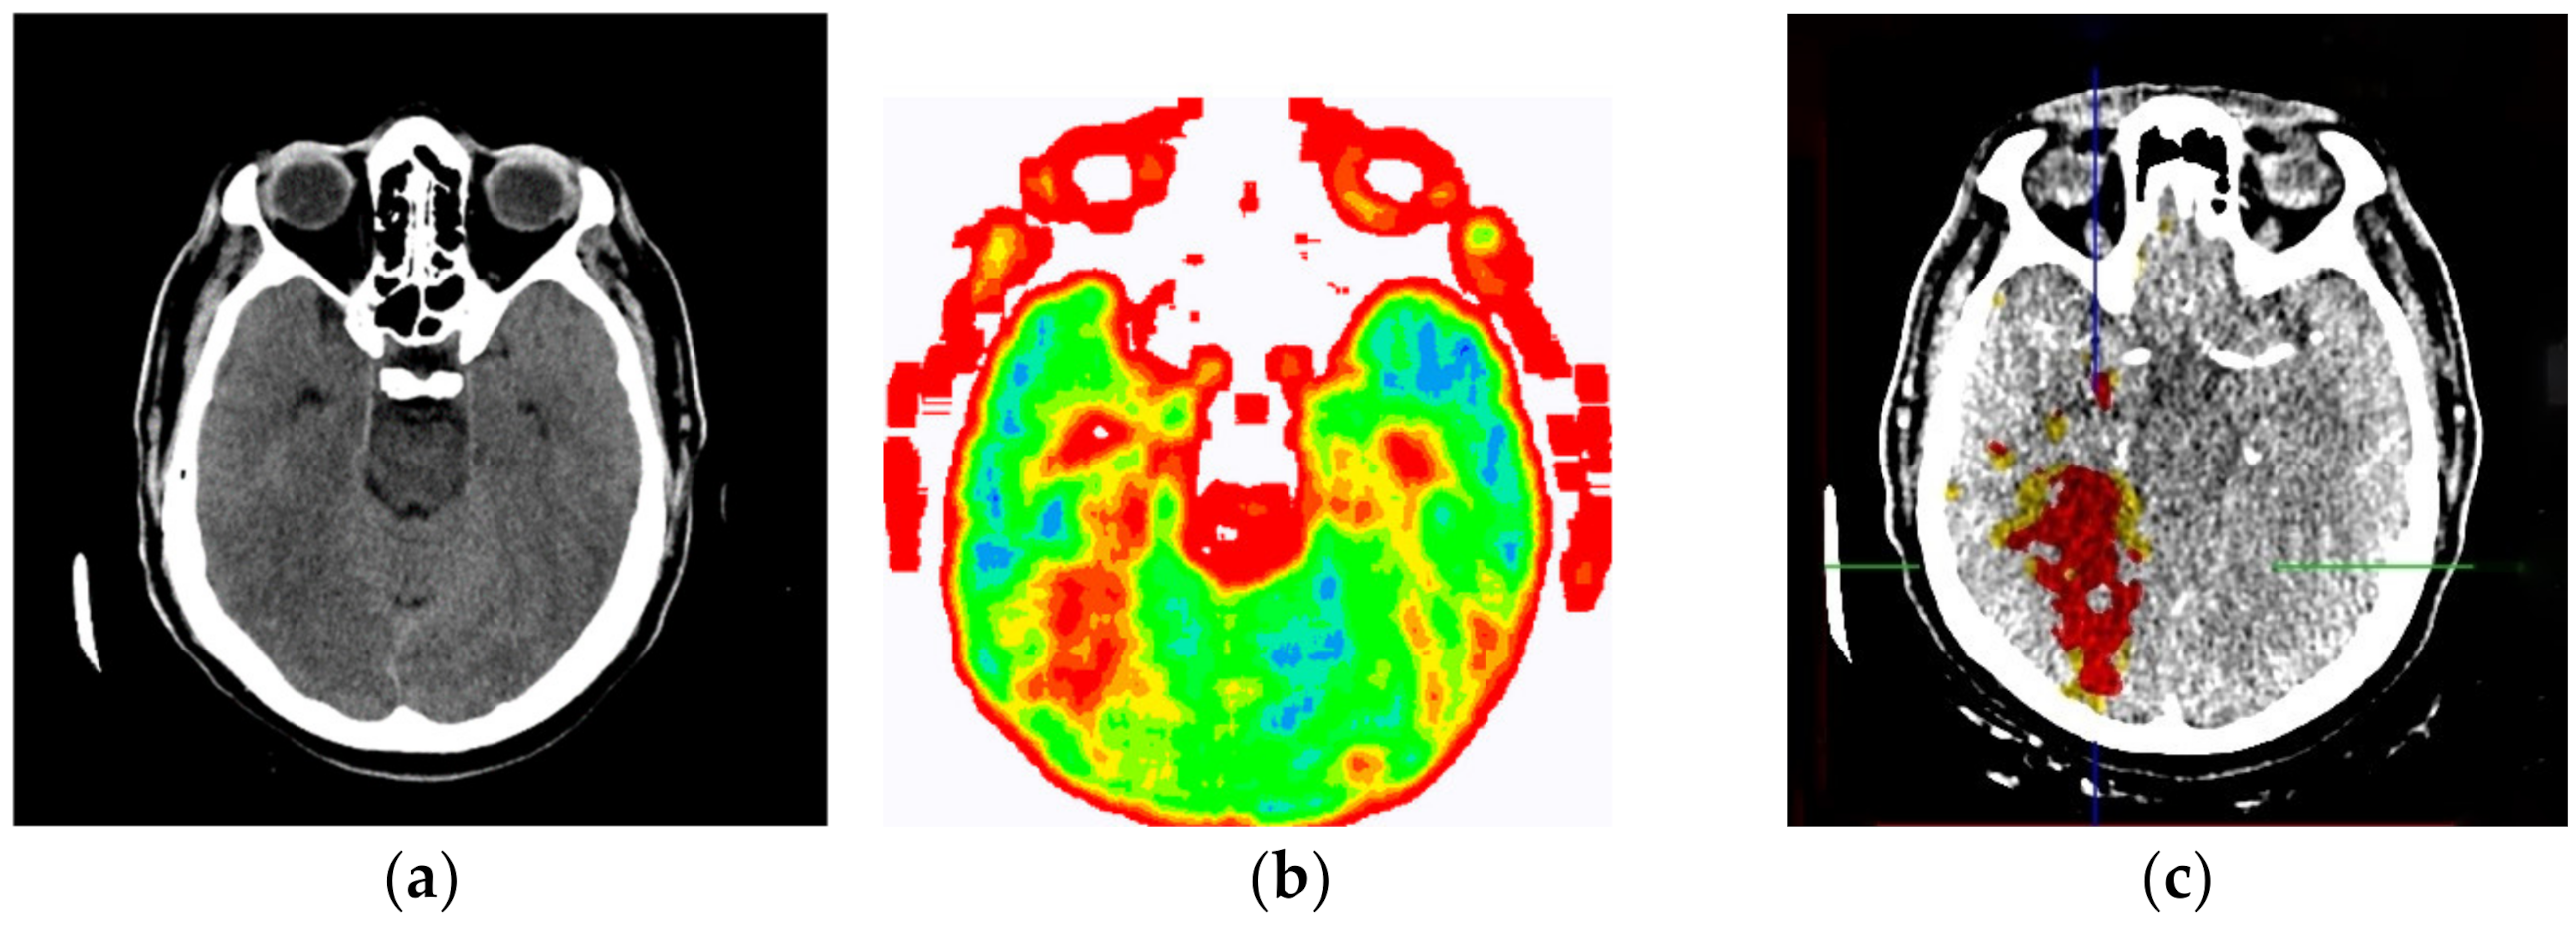

The evaluation of the developed model was conducted through an online questionnaire to determine whether smart visualization of medical images (SVMI) can contribute to the education of MDs in the radiology residency training program and undergraduate medical students. A total of twenty Physicians of the Department of Emergency Neuroradiology expressed their professional medical opinion when completing the questionnaire. Nine were neuroradiology/radiology specialists (45%) and eleven were MDs in the radiology residency training program (55%). All physicians agreed to participate in the research and did not have insight into the patient’s final diagnosis (Diagnosis of the disease after performing all the diagnostic methods provided by the protocol: Occipital right, in the region of PCA vascularization, observed zone of hypodensity, without differentiation of gray-white mass and flattened sulci diff.dg.acute ischemic stroke) after complete diagnostic methods, which included a post-contrast MDCT of endocranium, MDCT perfusion, and MDCT angiography. Therefore, a triple-blind review system was applied. No participants knew the physician’s opinion (before or after), or the patient’s official diagnosis, name, and surname, or the neuroradiologist who performed the examination. Additionally, all survey participants were asked questions according to the order of appearance of the images, starting with Figure 13a.

Figure 13.

(a) Non-contrast MDCT image of the endocranium; (b) SVMI of the non-contrast MDCT image of the endocranium; and (c) MDCT perfusion of the same cross-section.

Figure 13a shows a non-contrast MDCT image of the endocranium establishing a zone of hypodensity without clear differentiation of the gray–white mass on the occipital right, which corresponds to an acute ischemic lesion. Figure 13b presents our method of smart visualization of the medical images (SVMI) of the non-contrast MDCT image of the endocranium of the same cross-section. Figure 13c, after additional diagnostics of MDCT perfusion, shows a perfusion deficit that can be seen in the same region—occipital right—which confirms the diagnosis of an acute ischemic stroke.

On the presented non-contrast MDCT image of the patient’s endocranium (Figure 13a), 100% (nine) of radiology specialists noticed that changes in the brain had occurred based on their knowledge in the field of neuroradiology, which ranged from 3 to 15 years of experience for all radiologists who expressed their expert opinion. On the other hand, based on the non-contrast MDCT image of the endocranium (Figure 13a), 81.81% (nine) of the total number of MDs in the radiology residency training program who participated in the questionnaire did not notice the change, did not adequately characterize it, or did not give an adequate differential diagnosis. Table 1 shows the analysis of the physicians’ answers to the first question observing only Figure 13a.

Following smart visualization (SVMI) of the non-contrast MDCT image of the endocranium (Figure 13b), out of all physicians whose opinions were requested, 95% of respondents made an accurate diagnosis and confirmed the existence of pathological changes in density. However, one MD in a radiology residency training program answered incorrectly. Table 2 shows the analysis of the physicians’ answers to the second question observing only Figure 13b.

An analysis of the responses, in which 60% of physicians gave a statement that “it can” and 35% of physicians said that “to some extent it can,” argues that smart visualization of medical images (SVMI) can contribute to education. Additionally, the proposed SVMI model follows the clinical protocols for further diagnostics and patient treatment. For confirmation, Figure 13c shows MDCT perfusion in which a perfusion deficit is observed, articulating in favor of the existence of an acute ischemic stroke.